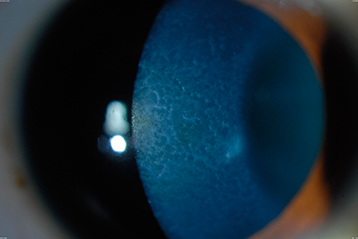

Most common anterior dystrophy. Diffuse gray patches (maps), creamy-white cysts (dots), or fine refractile lines (fingerprints) in the corneal epithelium, best seen with retroillumination or a broad slit-lamp beam angled from the side (see Figures 4.26.1 and 4.26.2). Spontaneous painful corneal erosions may develop, particularly on opening the eyes after sleep. May cause decreased vision, monocular diplopia, and shadow images. See 4.2, Recurrent Corneal Erosion, for treatment.